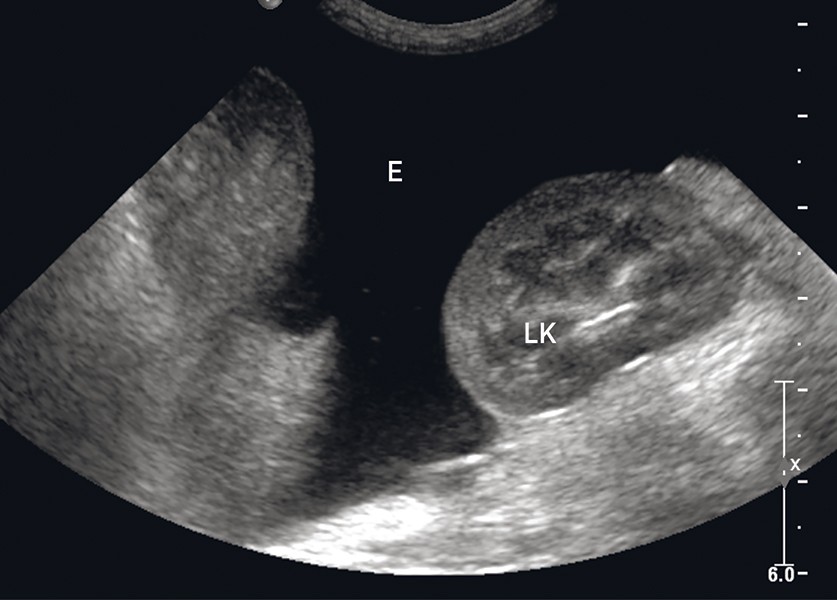

Investigatii clinice si paraclinice : Ecografie abdominala si ecografie toracica, hemoleucograma, biochimie sangvina complete si examen radiologic complet. In urma acestor investigatii s-a descoperit urmatoarele :

• Efuzie pericardica

• Efuzie abdominala